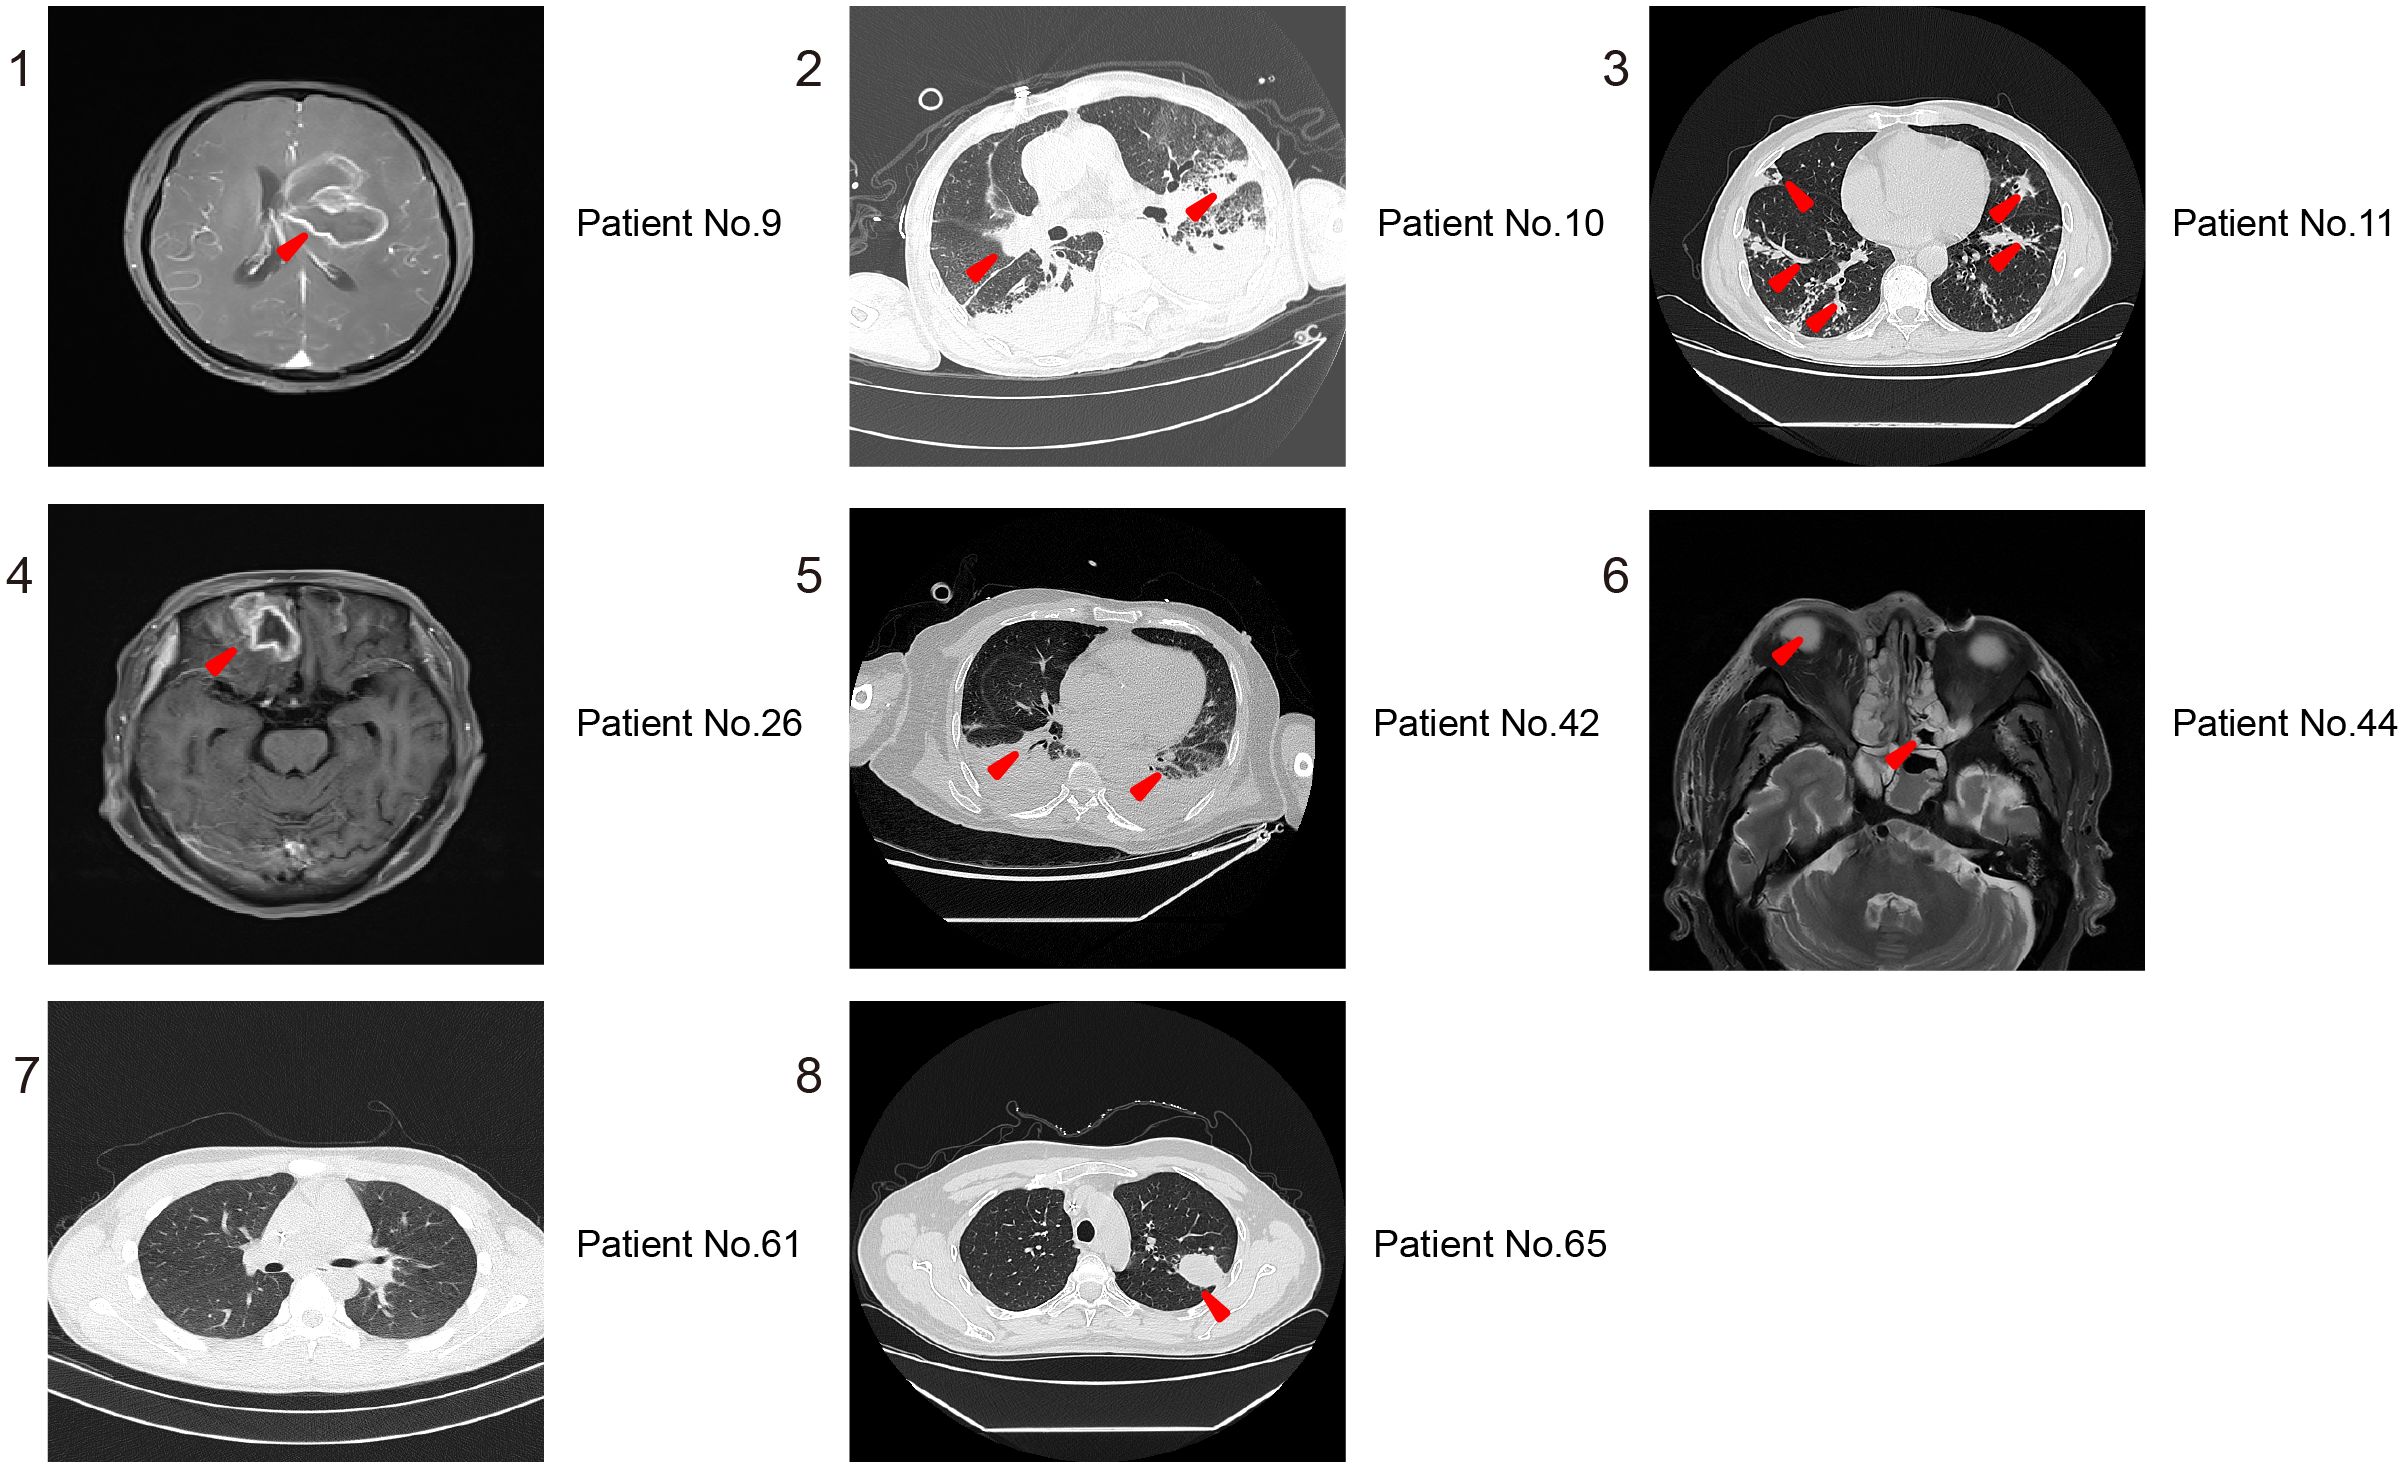

To evaluate the value of imaging in diagnosing Mucorales infection, we reviewed the imaging results of all cases. As shown in Figure 3, the Brain MRI of patient No.9 showed abnormal lesions, but it can’t indicate which pathogen caused it. Patient No.10 displayed a mixed infection, but cannot be distinguished. Patient No.61 presented no abnormalities. The remaining patients of No. 11, No. 26, No. 42, No. 44, No.65 are all not that obvious for Mucorales infection diagnosis. Altogether, it is difficult to determine whether the detected abnormalities are caused by Mucorales. Therefore, it is of great significance to combine other laboratory tests for the diagnosis of Mucorales infection.

Figure 3. Representative imaging results for distinguishing Mucorales infection from colonization. 1,4, and 6 are MRI of Brain; 2, 3, 5, 7, and 8 are CT of lung. The red arrowheads showed the abnormal lesions.

Numerous studies have investigated the diagnostic ability of mNGS for Mucorales infection, but there remains little research on the distinction of Mucorales colonization and infection (Wang et al., 2024; Zhang et al., 2024). Meaningfully, our study laid the foundation for the establishment of the positive threshold criteria according to different host and pathogen status in some ways. We observed that mNGS displayed superior accuracy in diagnosing Mucorales infection and distinguishing it from colonization when compared to culture and OMT (P < 0.05). The optimal cut-off value of RPTM for mNGS was 51. At this threshold, mNGS achieved a sensitivity of 58.82% and a specificity of 90.00% for the final diagnosis (Figure 2B). Furthermore, multiple (≥10) nodules, pleural effusion and halo sign were reportedly associated with pulmonary mucormycosis (Chamilos et al., 2005; Legouge et al., 2014). However, we found that imaging has limitations in diagnosing mucormycosis in clinical, especially when it comes to co-infection of multiple pathogens. Indeed, this research can serve as a valuable reference for analyzing patients with Mucorales infection and colonization. Notably, even though mNGS serves as a precise pathogen infection test method and has potential diagnosis in clinic, the final diagnosis of the disease counts on clinical experts who integrate the patient’s symptoms, clinical laboratory test results, and etiological findings to make a comprehensive decision. And in the future, it is necessary for us to conduct prospective studies with a large amount of data about distinction of Mucorales infection and colonization.